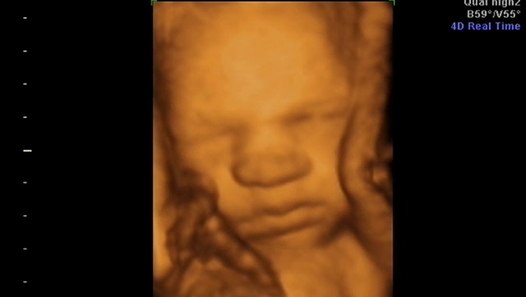

4d Ultrason Goruntuleri Hareketli Renkli Ultrason Anne Karninda Bebek Resimleri